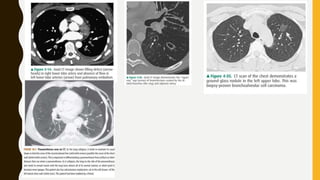

CT CHEST

• Haemothorax, pneumothorax

• Detect both acute and chronic changes in lung parenchyma